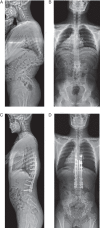

This paper presents a highly challenging technique involving posterior double vertebral column resections (VCRs) and satellite rods placement. This was a young adult case with severe angular thoracolumbar kyphosis of 101 degrees, secondary to anterior segmentation failure from T11 to L1 . There were hemivertebrae at T11 and T12 , and a wedged vertebra at L1 . He received double VCRs at T12 and T11 and instrumented fusion from T6 to L4 via a posterior only approach. Autologous grafts and a cage were placed between the bony surfaces of the osteotomy gap. Once closure of osteotomy was achieved, bilateral permanent CoCr rods were placed with addition of satellite rods. Postoperative X-ray demonstrated marked correction of kyphosis. On the 10(th) days after surgery, the patient was able to walk without assistance. In conclusion, double VCRs are effective to correct severe angular kyphosis, and addition of satellite rods may be imperative to enhance instrumentation strength and thus prevent correction loss.